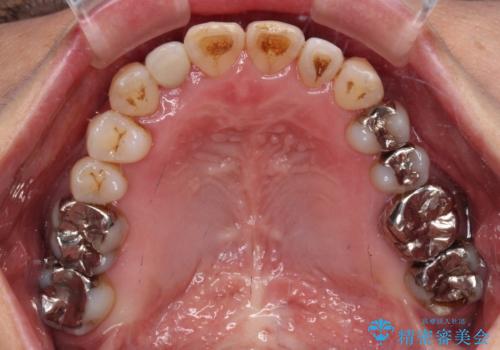

- 前歯の反対咬合を気にして来院された患者様です。

上顎骨の幅が下顎骨よりも小さいので、拡大装置により骨幅を広げて上下関係を改善すると同時にワイヤー矯正で反対咬合の改善を図り、その後インビザラインにて歯並びを整えることとしました。

上顎前歯の矮小歯は矯正治療の途中でオールセラミッククラウンを装着し、左右のバランスを整えることとしました。

急速拡大装置の使用により奥歯の咬み合わせが劇的に変わり、その変化を利用して反対咬合を改善することができました。

治療期間中は奥歯が咬み合わず、食事が取りにくいなどの不都合がありましたが、最終的にはきれいに整えることができました。